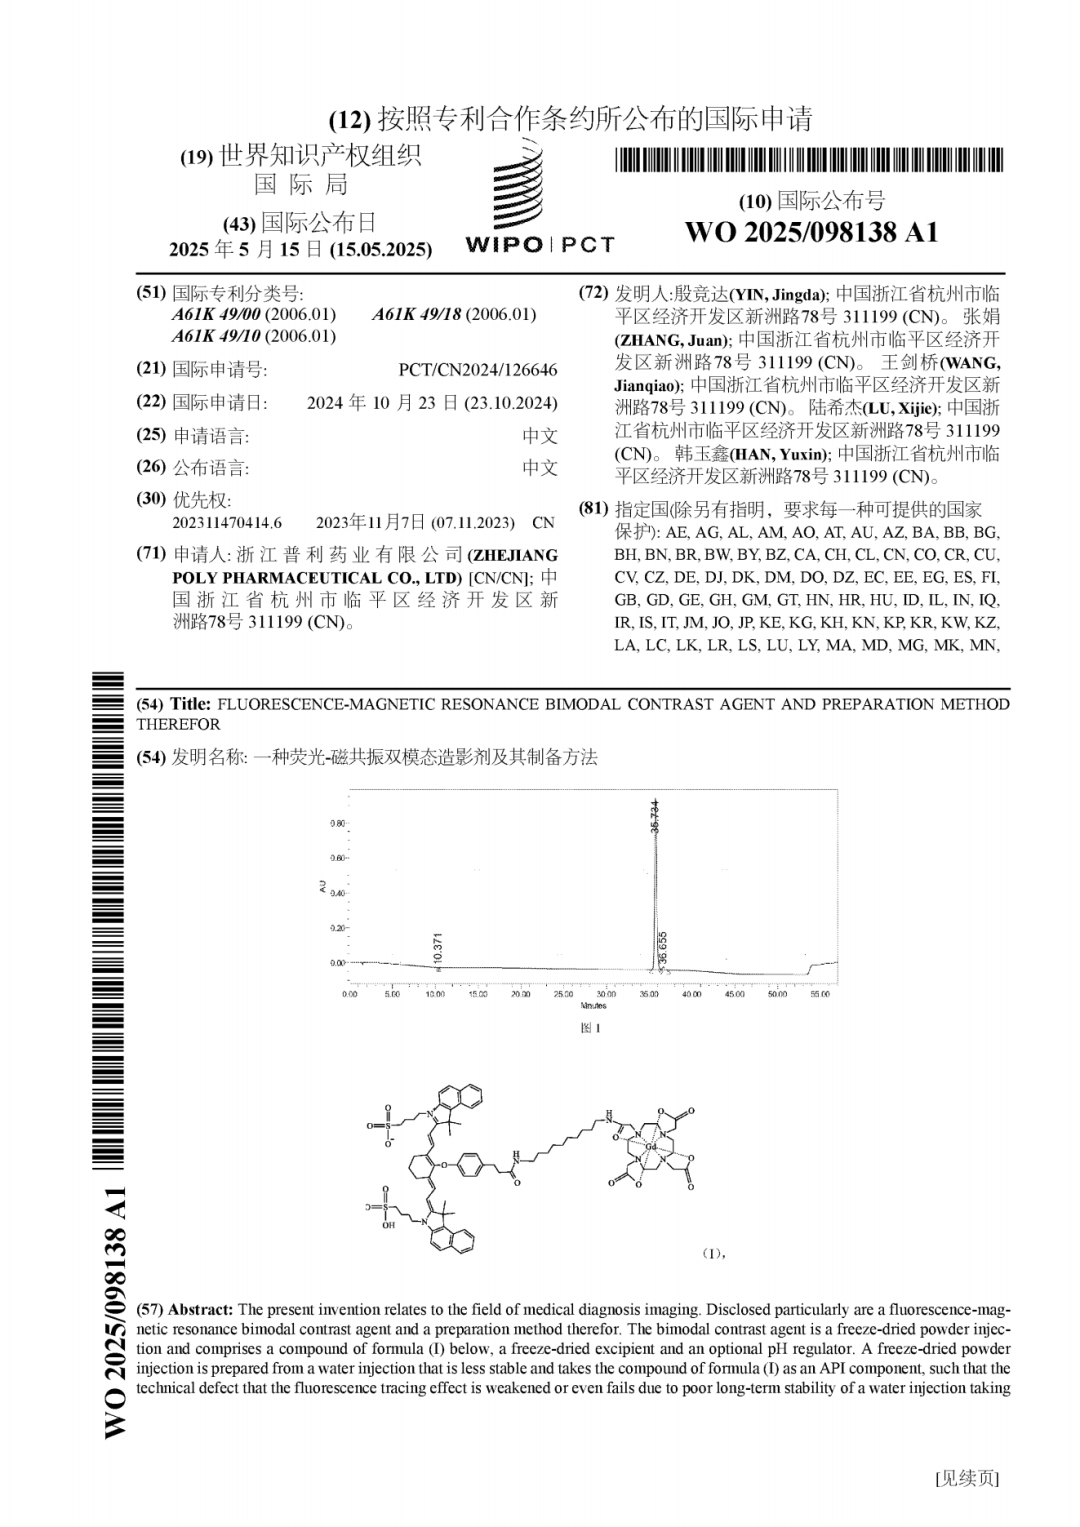

近日,爱游戏体育APP网站/手机版下载/官网登录入口 全资子公司浙江普利药业有限公司的一项PCT专利,“一种荧光-磁共振双模态造影剂及其制备方法(WO 2025/098138 A1)” 对外公开。该项专利为双模态造影剂创新药PL002的制剂专利。至此,普利制药关于PL002已有4项中国专利,2项PCT专利获得公开。

2023年10月,PL002获得FDA签发的美国药物临床试验批件,用于原发性肝癌患者的术前诊断及术中导航。2024年11月,PL002获得中国药物临床试验批准,用于脑胶质瘤患者的术前诊断及术中导航。这是普利制药第一张国际和国内造影剂创新药临床批件。普利制药关于PL002在专利保护方面同样进行了布局,目前已有4项中国专利,2项PCT专利获得公开。